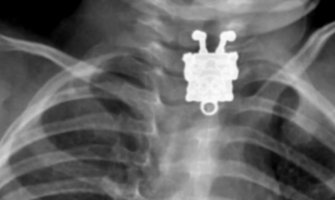

Doktor iz Saudijske Arabije doživio je šok kada je na rendgenskom snimku tijela 16-mjes...